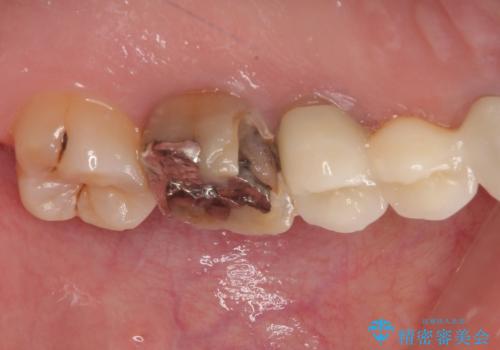

- 冷たいものがしみることがあるとのことで来院された患者様です。

銀歯の下にまでむし歯が及んでおり、レントゲン写真からも神経組織に迫っている状態が確認されました。

稀に冷たいものがしみる程度で、術前診査では神経を全て取る可能性は低いと予想されましたが、一部切除する可能性が高いことを伝えた上で治療を行うこととしました。

銀歯や欠損が大きいことから、虫歯治療後はオールセラミッククラウンによる補綴治療を行うこととしました。